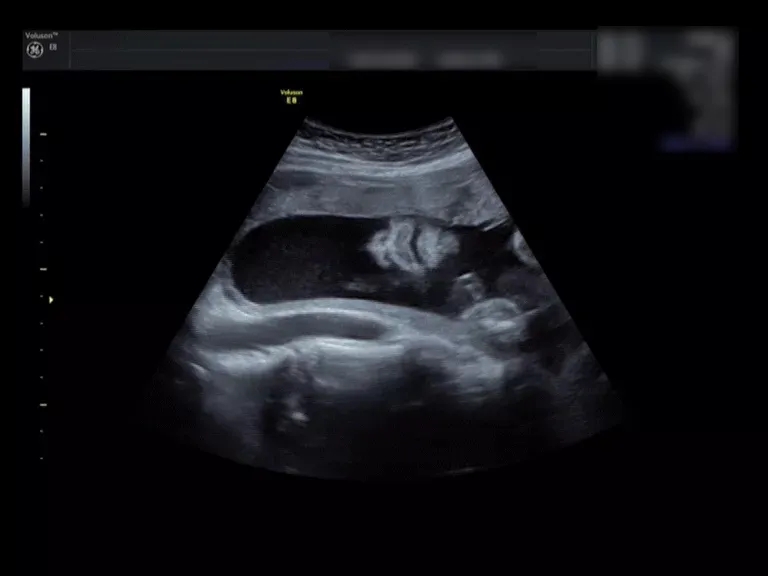

来看这个小baby的彩超对比

就一目了然啦

(二维超声)